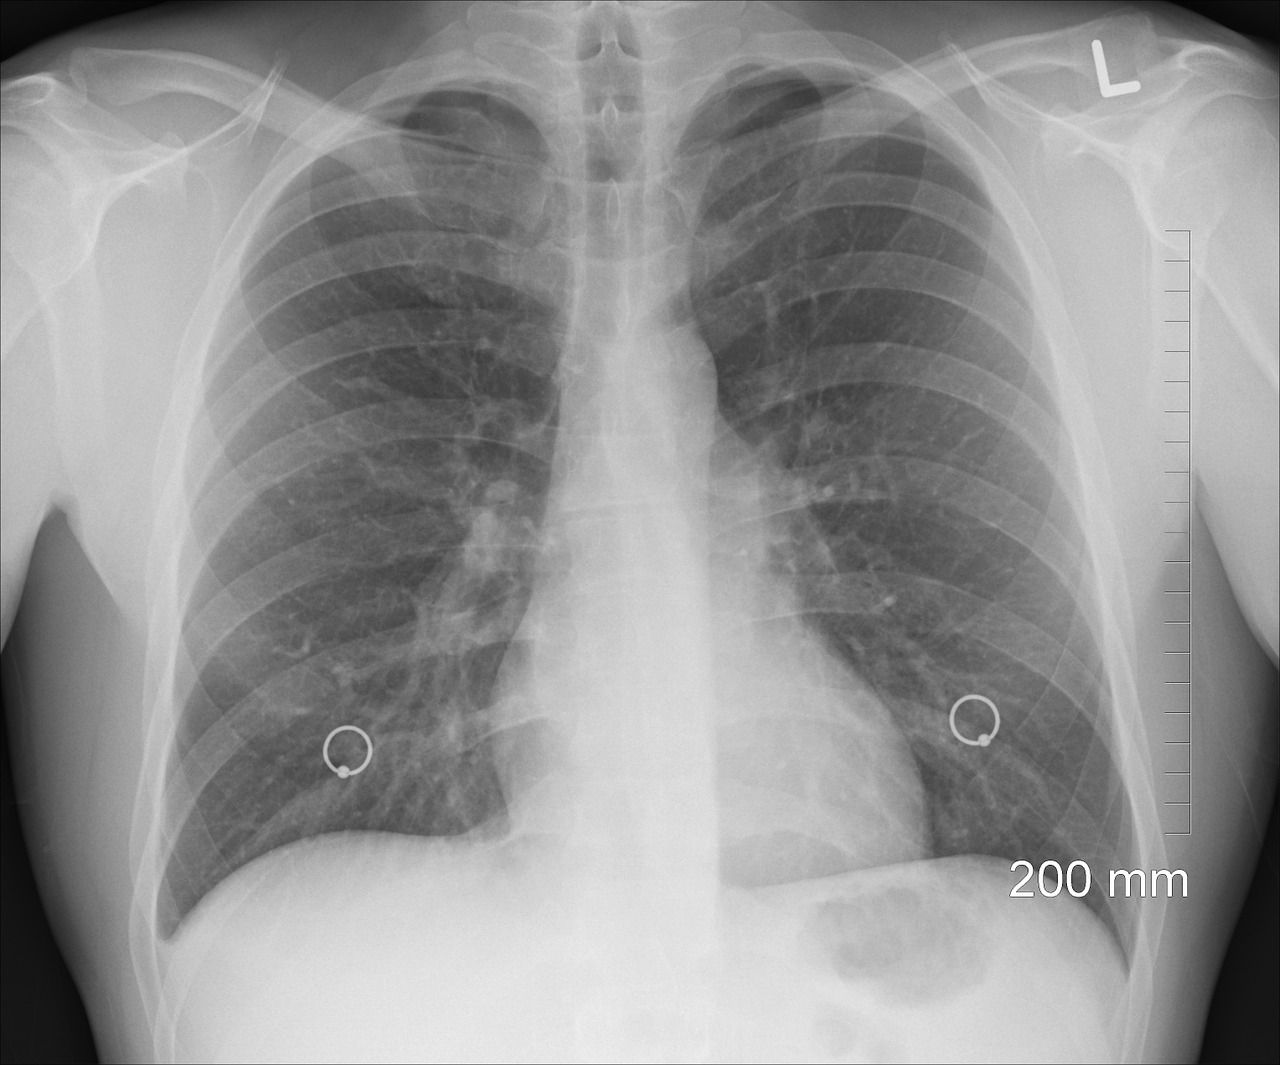

专家周二表示,匈牙利有 30 万哮喘患者接受医疗护理,估计有 15 万哮喘患者患有这种疾病。

匈牙利每年有 15,000-20,000 名患者被诊断患有哮喘,15,000-30,000 名患者患有慢性哮喘。,

布达佩斯塞梅尔维斯大学肺科医生莉拉·塔马西在世界哮喘日表示,并补充说慢性病患者接受先进的治疗。

50%左右的哮喘患者未能定期服用药物,其中90%由国家健康保险基金支付,该大学肺科诊所副主任Tamási说。